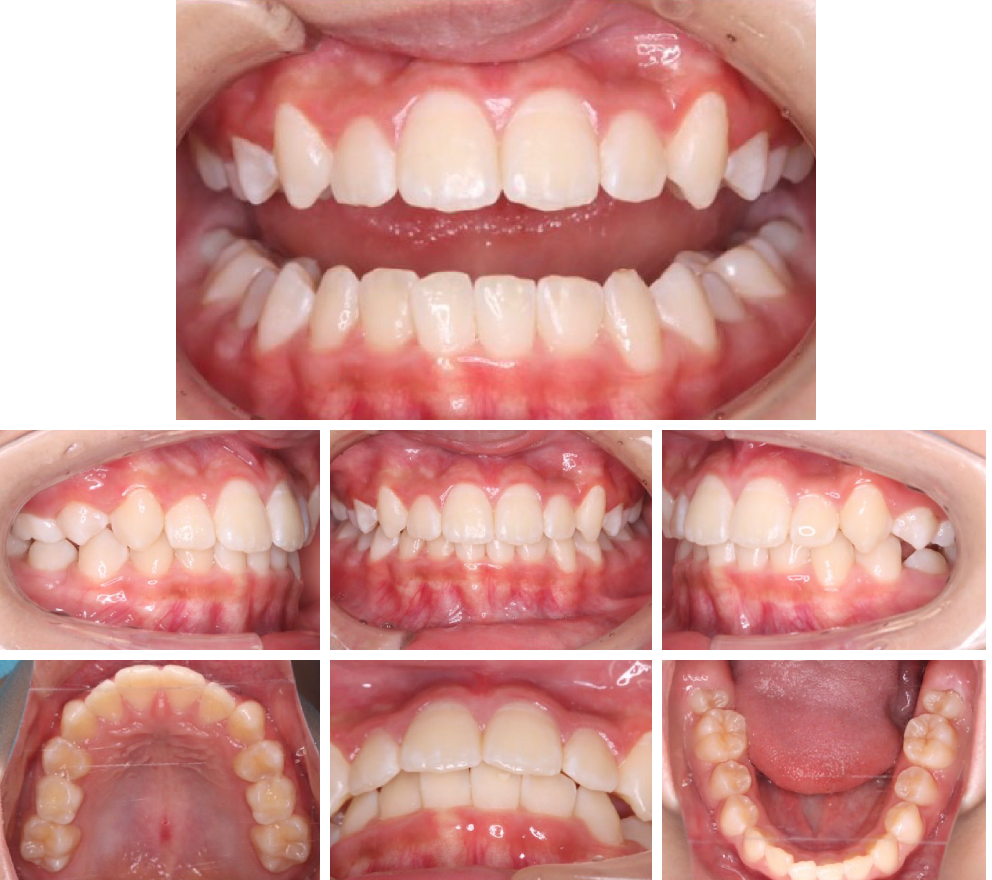

当院の症例

CASE